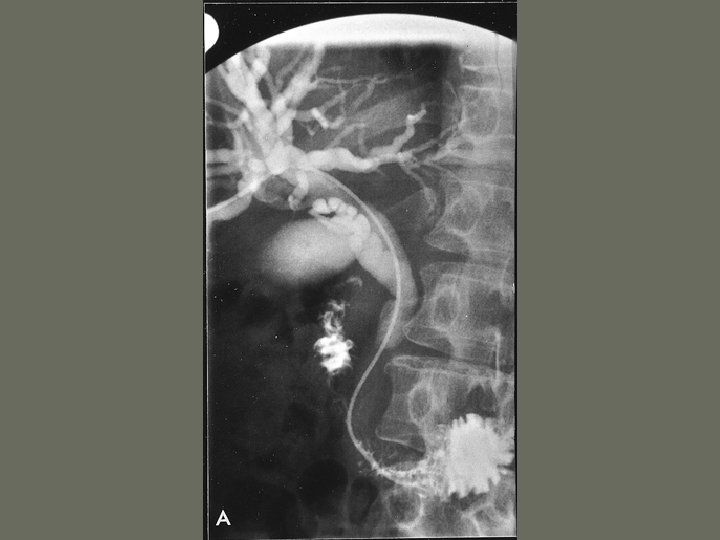

Interventional Procedures • Non-vascular procedures include: 1. Percutaneous Nephrostomy Tube – catheter is introduced through the _____, into the kidney and into the renal pelvis – may be used to remove _____, drain fluid or other interventions

Interventional Procedures 2. Percutaneous Biliary Drainage • internal or external drainage of ______, stone removal, dilation of obstructed bile duct and biopsy • catheter placed within the biliary ____ with a bag attached to the catheter outside the body

Interventional Procedures 6. Ureteric Stent Placement • Inserted in ureter • performed after a percutaneous nephrostomy • used on patients with ________ of the renal system

Interventional Procedures 7. Percutaneous Lithotripsy • extracorporeal shock wave lithotripsy (ESWL) • renal stone is obliterated until they are ______ enough to pass through the urinary system